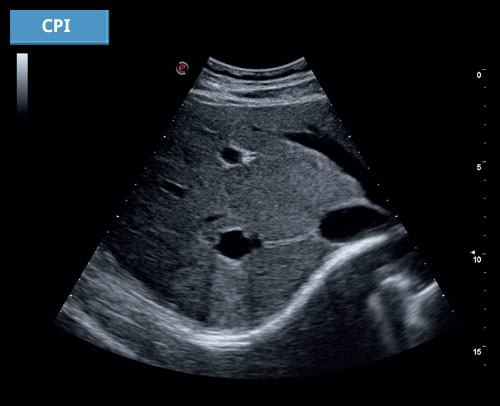

CPI

Obtížně vyšetřitelní pacienti jsou v dnešních ordinacích docela běžní. Technologie CPI společnosti Esaote pomáhá při řešení těchto výzev a umožňuje sonografům získávat detailní snímky i u obézních pacientů a v hlubších vyšetřovacích oblastech.